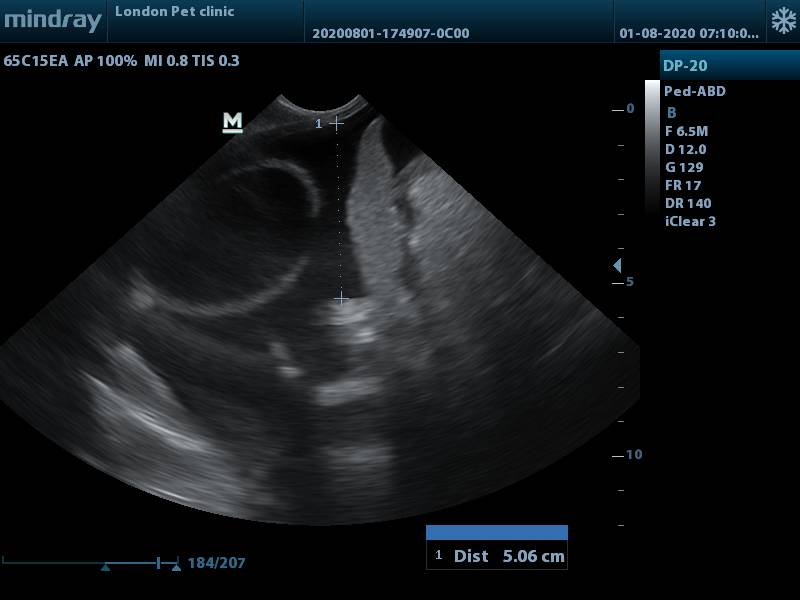

Ultrasound:

Can detect free abdominal fluid

shows bladder wall defect ( not intact )

ultrasound shows uroabdomen with impaired bladder wall integrity